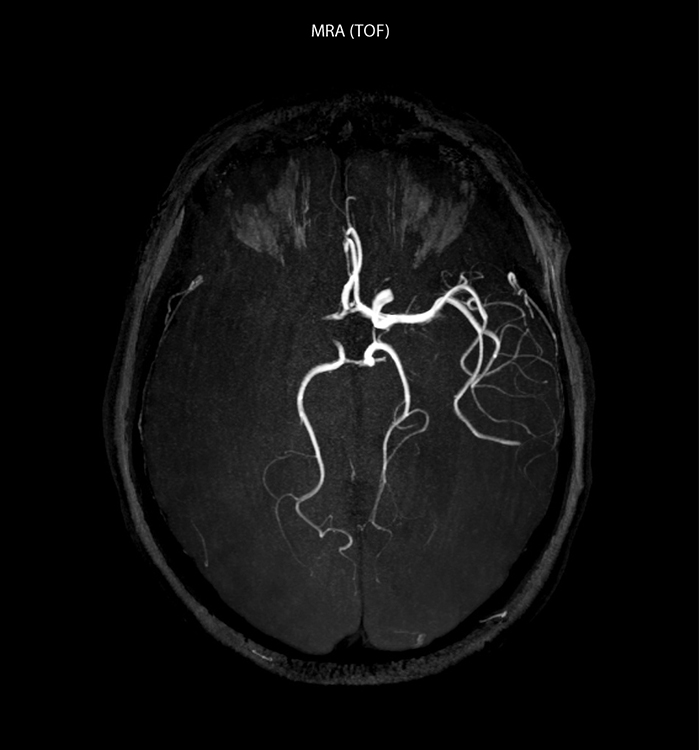

“In France, stroke is usually imaged with MRI, not CT, even for emergency treatment. This is because MRI helps us directly visualize ischemia in the acute phase, but can also help rule out differentials such as MS and hematoma. In addition, we can assess the intracranial and extracranial vessels during the same examination,” says Dr. Savatovsky.

The first challenge in MRI of stroke is speed. The patient typically arrives from an ambulance in the MRI preparation room and the installation is done on a separate dock outside the scanner room. “The venous access is placed during the neurological examination. If the delay from the first symptoms allows the patient to receive thrombolysis we do a very fast examination that typically lasts about 11 minutes including the pre-scans. In the case of transient ischemic stroke we usually add ASL perfusion because in some symptoms with negative diffusion, ASL sometimes indicates a vascular origin.”

“Ingenia provides great flexibility in the parameters setting. We can tune a sequence the way we want,” says Dr. Savatovsky. “For example, in a stroke exam we use a FLAIR sequence of about two minutes instead of the four-minute FLAIR we use for MS. The diffusion is 30 seconds, the T2*-weighted scan is 30 seconds, the angiography scan time is less than one minute. Ingenia is a great scanner in that situation; even with these fast sequences we can achieve good images with good SNR. When the first sequence tells us that it’s not an ischemic stroke but a hemorrhagic stroke, we may switch to a time-resolved angiography to look for vascular malformations and venous thrombosis.

The ideal stroke protocol?

“Every center is different, but for me the ideal protocol for stroke includes diffusion weighted imaging, FLAIR, and fast susceptibility imaging,” says Dr. Savatovsky. “Our fast susceptibility weighted imaging takes 50 seconds, so it’s as fast as T2*-weighted imaging. It visualizes hemorrhage but also the clots. We also do 3D MR angiography that provides information on cervical and brain vessels. If the patient does not need immediate treatment, or if additional information is needed to decide on treatment, we might also add perfusion imaging and post-contrast T1-weighted imaging.”